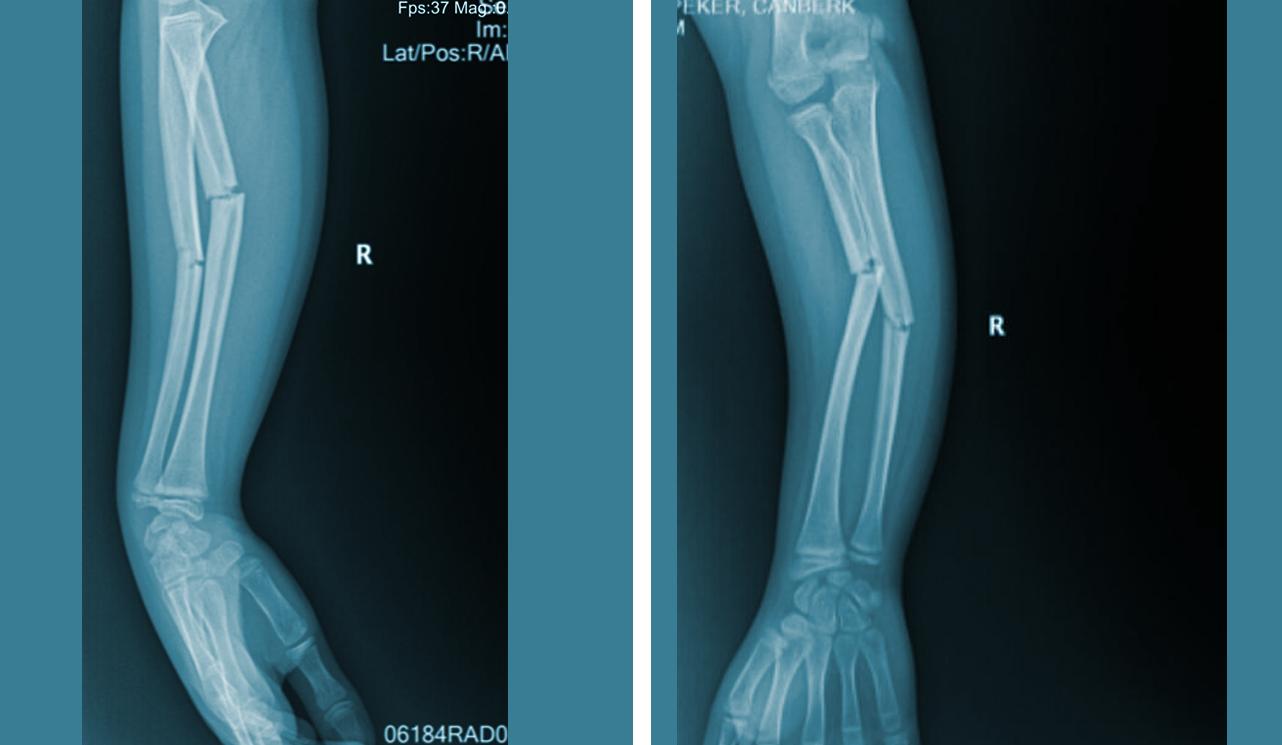

Ortopedik cerrahinin bir alt uzmanlığı olarak kabul edilir ve kırık kemiklerin tedavi edilmesine ve vücudun yaralı kısmının yaralanmadan önce sahip olduğu orijinal gücüne ve maksimum işlevine geri dönmesini sağlamaya odaklanır.